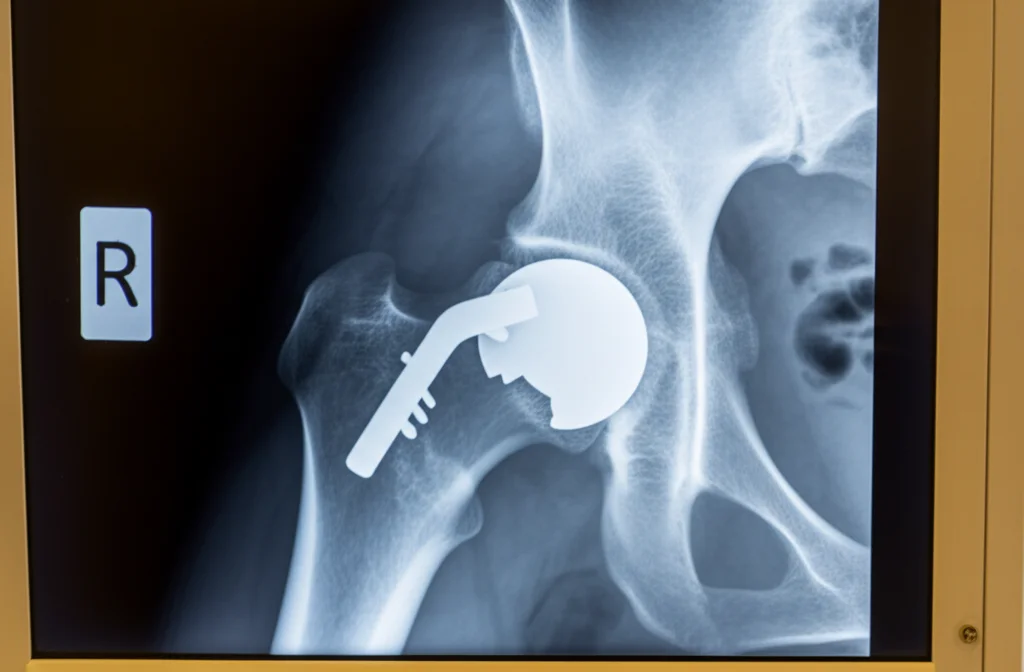

Fratture Vicino alla Protesi d’Anca? Spesso è l’Ombra dell’Osteoporosi

Ciao a tutti! Oggi voglio parlarvi di un argomento che tocca da vicino molti di noi, direttamente o indirettamente: le protesi articolari, in particolare quelle d’anca, e una complicanza che può sorgere, le fratture periprotesiche femorali (PFF). Parliamoci chiaro, l’aumento dell’aspettativa di vita e il desiderio, più che legittimo, di mantenere una buona mobilità e qualità della vita hanno portato a un boom di interventi di artroplastica totale. Pensate che negli USA si prevede un aumento del 300% per le protesi d’anca (THA) entro il 2040! Numeri impressionanti, vero?

Ma come in tutte le cose belle, c’è anche un rovescio della medaglia. Le complicazioni esistono, e tra queste, le fratture che avvengono proprio intorno all’impianto protesico, le PFF appunto, sono una delle cause più comuni di revisione chirurgica dopo una protesi d’anca. Si stima che possano interessare fino al 18% dei pazienti dopo il primo intervento, con un rischio che aumenta di anno in anno. E non è solo una questione di dover tornare sotto i ferri: la mortalità a un anno da una PFF è paragonabile a quella delle fratture osteoporotiche “classiche”, variando tra il 10% e il 36%. Un dato che fa riflettere, anche considerando l’impatto economico non indifferente.